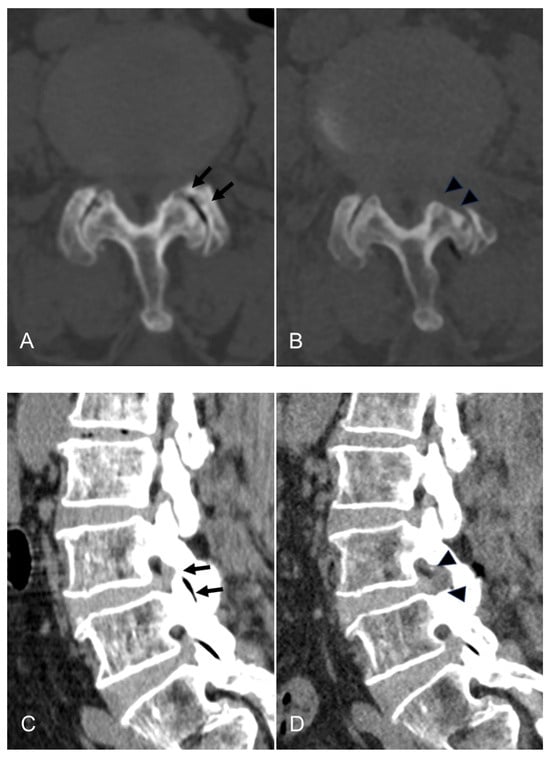

Figure 3.

An illustrative case of an 81-year-old female patient treated with TELLRD. (A) Preoperative axial CT showing central and lateral recess stenosis at the L3–L4 level (arrows). (B) Postoperative axial CT showing lateral spinal canal decompression following undercutting of the hypertrophic SAP and LF compressing the TNR (arrowheads). (C) Preoperative sagittal CT showing lateral recess stenosis at the L3–L4 level (arrows). (D) Postoperative sagittal CT showing lateral spinal canal decompression following undercutting of the hypertrophic SAP and LF compressing the TNR (arrowheads). (E) Postoperative coronal CT showing lateral recess stenosis at the L3–L4 level (arrows). (F) Postoperative coronal CT showing lateral spinal canal decompression following undercutting the SAP and LF compressing the TNR (arrowheads). TELLRD, transforaminal endoscopic lumbar lateral recess decompression; SAP, superior articular process; LF, ligamentum flavum; TNR, traversing nerve root.